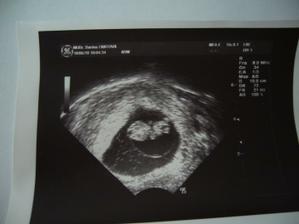

4.6. na utz potvrzena srdeční akce a byla jsem předána své dr.

18.6. vše ok, mimi odpovídá 9+6tt